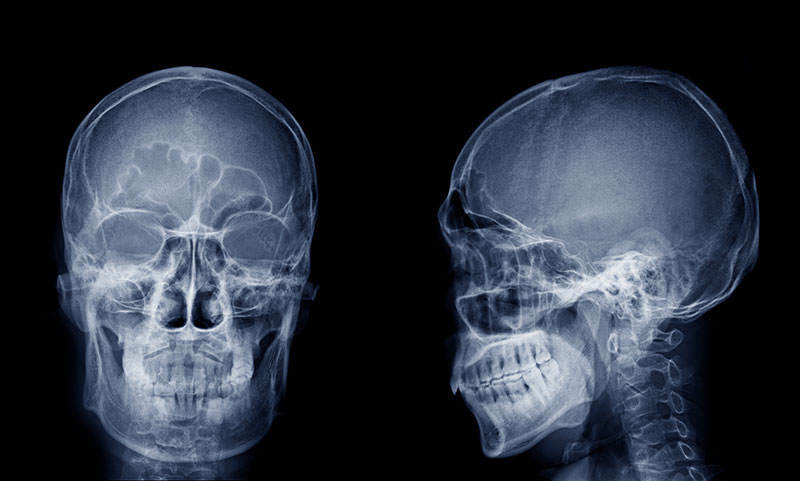

頭部X線規格写真

(セファログラム)

睡眠時無呼吸症候群は症状の重さにより治療法が異なります。軽度から中度であれば、マウスピースなどの簡易的な装置を用いた自宅での治療が可能です。一方、重度であれば顎顔面形成術や舌骨上筋群牽引術といった治療が必要となるケースも。

その判断に使われるのが頭部X線規格写真(セファログラム)です。腔内や気道の状態を確認できるため、睡眠時無呼吸症候群の原因や深刻度などを総合的に判断できます。